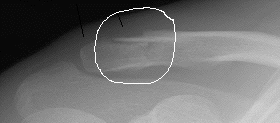

旅帰りの翌日、骨折45日目、またまた某病院に夜潜入、飯塚選手の診察。良好の模様。

上部の方が形成が遅いが

大分骨が出来てきた。